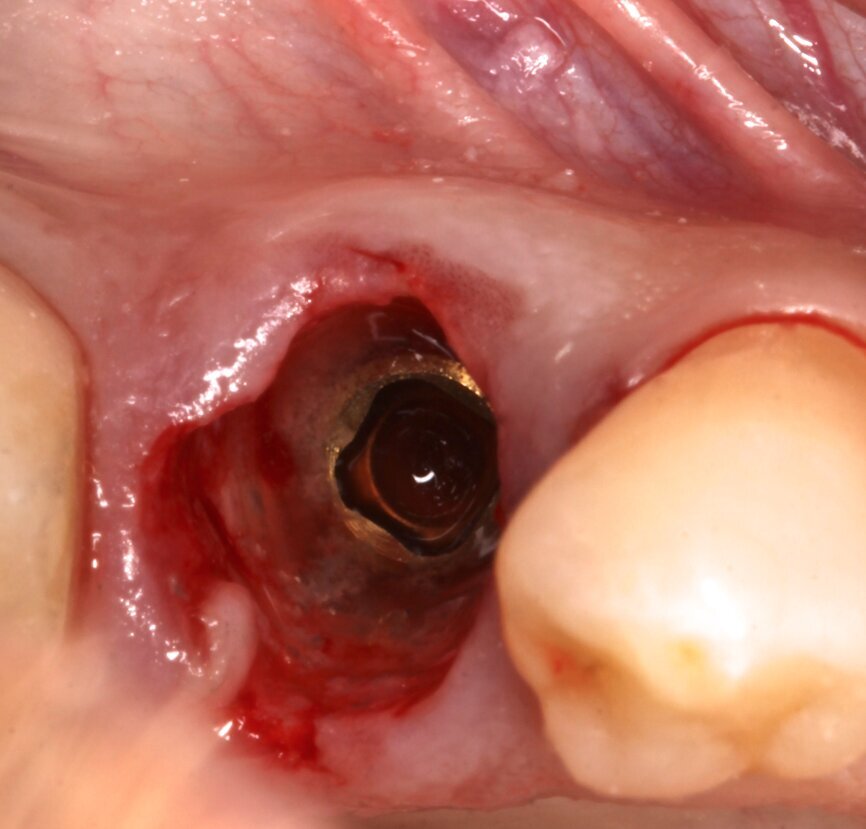

Fig. 3: Implant without intermediate abutment.

A 5 x 15 mm BTI interna plus implant (internal connection) was placed lingually to the SS, taking as reference for 3D positioning the adjacent tooth and implant crowns. The platform of the implant was placed 1 mm below the level of the buccal bone crest and the SS (Fig. 3). A BTI UNIT Transepithelial abutment was used to extend the implant’s platform 0.5 mm subgingivally (Fig. 4).